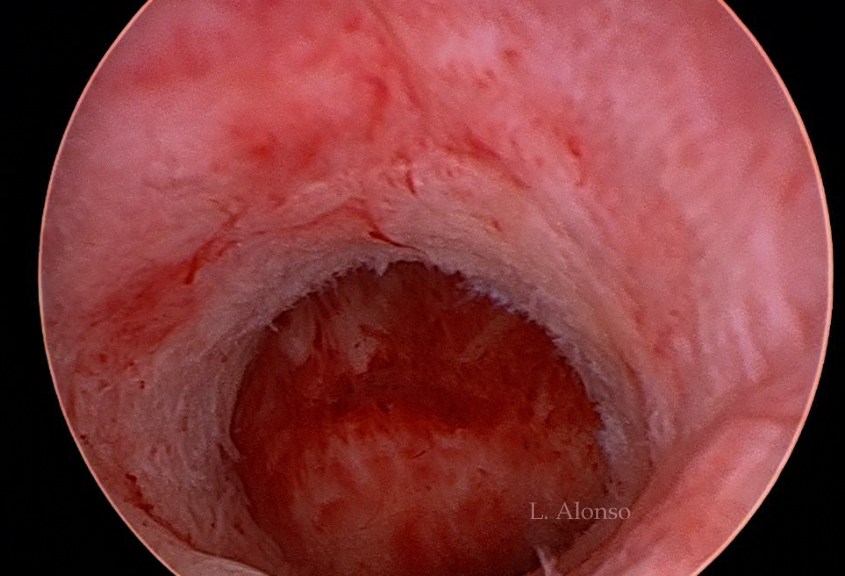

Category: cesarean scar defect